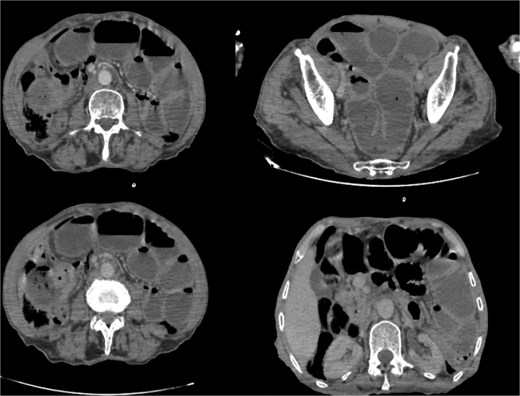

Biological tests were normal, but C-reative protein levels were slightly elevated at 24.20 mg/l (reference value <5 mg/l). Abdomino-pelvic scan, showed a dilated jejunum and ileum up stream of an ileal wall thickening, with minimal free fluid in the pelvis (Fig. 1).

Abdominal computed tomography scan showing dilated jejunal loops; (*): Ileal mass.